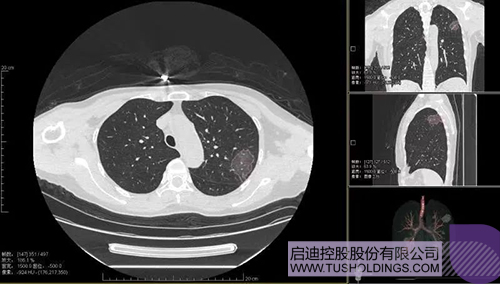

2020年2月11日,开云手机入口_开云(中国)科服投资企业—神州德信推出新冠肺炎检测及量化智能分析系统,积极助力一线医务人员科学精准防疫。